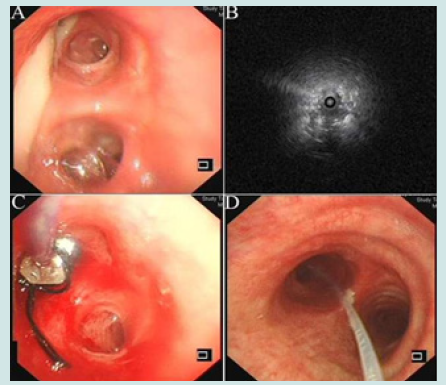

On 7 June 2021, the patient was referred to our department and underwent relevant examinations. Physical examination showed good healthy condition, but the lesion was solidly enhanced compared to the previous CT (Figure 2). Combined with the patient’s previous examination results, he was diagnosed with left CPA. The patient was unable to undergo surgical resection due to adhesions in the chest wall and poor lung function. We decided to infuse amphotericin-B into the left upper lesion under the guidance of R-EBUS. First, the bronchoscope was passed through the nasal approach into the trachea and local anaesthesia was performed by injecting 2% lidocaine (<15 ml) into the trachea/right and left bronchi through a bronchoscopic biopsy forceps. A white secretion from the posterior segment of the left upper lobe tip (Figure 3A) is flushed and cleaned. Then, a sterile catheter was placed into the tip of the left upper lobe of the lung with a guide wire and secured in the bronchus with a rubber plug under R-EBUS guidance (Figures 3B & 3C). Prior to administration, we reconfirmed that the position of the catheter had not moved by direct auscultation or CT. Then 5 mg of amphotericin B was dissolved in 10 ml of saline and injected into the left bronchus via the catheter within 5 minutes. The same dose of drug was administered once daily for four days. The catheter and rubber plug were removed after the fourth intrabronchial instillation of amphotericin B. A total of 20 mg of amphotericin B was administered during the treatment period and oral voriconazole was continued after discharge.

Figure 3: 3A. Preoperative tracheoscopic image showed a large purulent secretion. 3B. R-EBUS localization image. 3C. Tracheoscopic image during catheterization. 3D. Tracheoscopic image 5 days after catheterization (carina) showed a fewer granulation tissues.

However, he developed fever after endobronchial instillation of amphotericin B, was given appropriate antipyretics, and granulation tissue proliferated 5 days after catheter placement (Figure 3D) without other significant systemic or additional complications. After 1 month of follow-up, a CT scan showed vacuolation of the left upper lobe lesion, forming an air moon sign (Figure 4), and the necrotic area had been resorbed. In addition, the patient’s haemoptysis had stopped and he recovered well. After discharge, the patient decided to stop taking oral voriconazole on his own after one month. To date, the patient is in good health with no clinical recurrence.